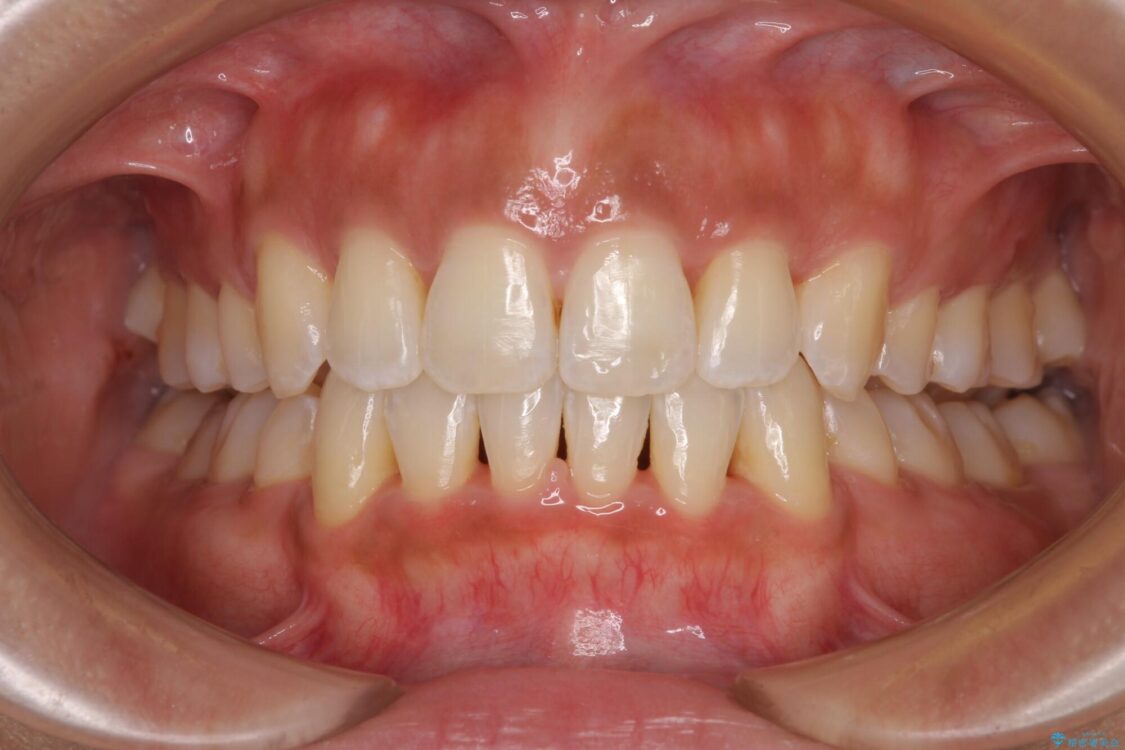

治療後について

抜歯スペースに前歯を移動させることで歯の突出感が改善され、非常に唇が閉じやすい仕上がりとなりました。

治療後

• 抜歯矯正で唇を閉じやすく 目立たないワイヤー装置 治療後画像